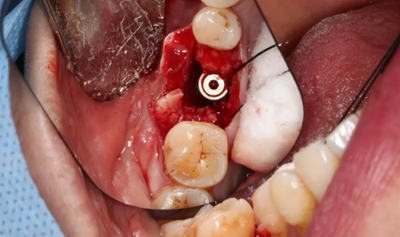

14、植骨手術(shù)過(guò)程

刮除肉芽組織及種植體表面清潔后,種植體唇側(cè)骨缺損區(qū)植入人工骨粉。

(攝于2017年8月10日)

引導(dǎo)骨再生

無(wú)張力間斷縫合切口。